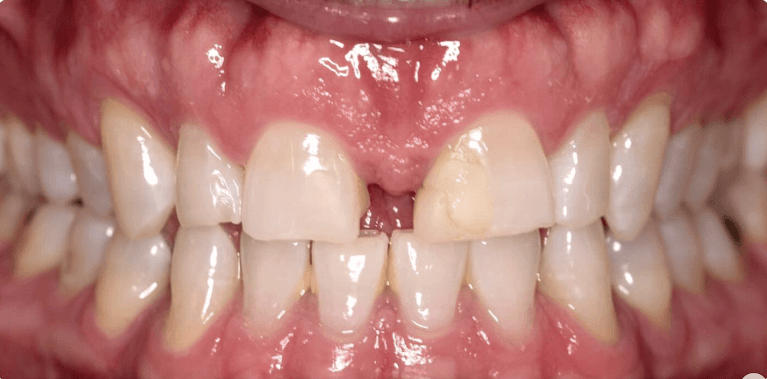

White spot treatment with Icon and mild spacing correction with Invisalign(5weeks only)